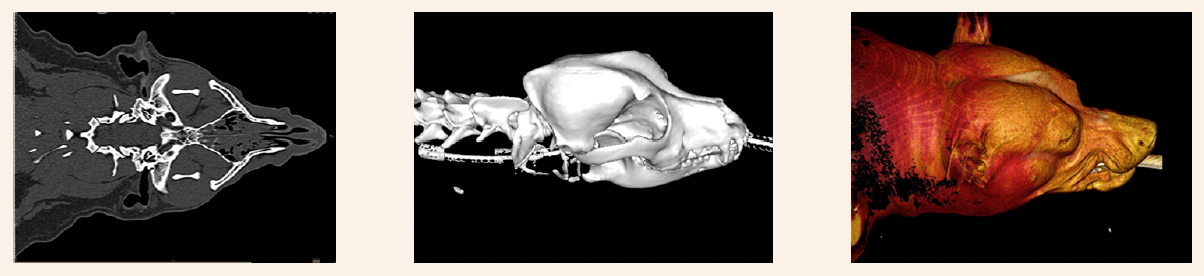

Imaging case study examples showcasing the advanced detail possible with modern CT and 3D reconstruction techniques. Images courtesy of Sage Veterinary Imaging